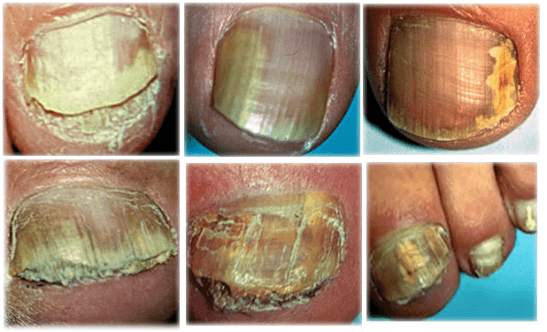

იცით რამდენი ადამიანი გარდაიცვალა სოკოვანი ინფექციით 2023 წელს? გასულ წელს საქართველოში 55 000 ადამიანი დაიღუპა. მათგან 31 000-ს ფეხის სოკო ჰქონდა. ეს მაჩვენებელი ყველა დაღუპულთა ნახევარზე მეტს შეესაბამება. ფრჩხილის სოკო არა მხოლოდ ფეხის ფრჩხილებს აზიანებს, არამედ შედის სისხლში და ვრცელდება ტერფებით მთელ სხეულზე. სოკო ანადგურებს ჩვენს სხეულს შიგნიდან და იწვევს სტრესს ყველა ორგანოში. მცირე სპორები ემაგრება შინაგან ორგანოებს და მრავლდება, რაც იწვევს სხვადასხვა სახის დაზიანებას. ამიტომ სოკოვანი ინფექციით ზიანდება შინაგანი ორგანოებიც. ეს ნიშნავს, რომ სხეული შიგნიდან "ლპება". დროთა განმავლობაში შეიძლება გული გაუმართოს, თავის ტვინში სისხლძარღვი გასკდეს ან განვითარდეს ღვიძლის კიბო. ასევე შესაძლებელია თირკმლის უკმარისობა. ყველას, ვისაც ფრჩხილის სოკო აწუხებს, რისკის ქვეშ იმყოფება. იმუნური სისტემა დასუსტებულია ხშირი გაციების გამო და სტრესი დანარჩენს აკეთებს, რაც იწვევს უეცარ სიკვდილს.

სწორედ ამიტომ მივიჩნევ ფეხის ფრჩხილის სოკოს უკიდურესად საშიშ დაავადებად, რომელიც იწვევს სიკვდილიანობის დიდ რაოდენობას ქვეყნის მასშტაბით. ჩვენ ხშირად გვესმის კიბოსა და სიმსივნეების შესახებ, მაგრამ საბოლოო ჯამში ისინი მხოლოდ 3-4%-ს აღენიშნება, მაშინ როცა ფრჩხილის სოკო 40-დან 80 წლამდე ასაკის ადამიანების 70%-შია.

ფოტოს ჩვენება

ფოტოს ჩვენება

ფოტოს ჩვენება

ფოტოს ჩვენება

სოკოს გარეგანი სიმპტომები საკმაოდ განკურნებადია, მაგრამ ეს არ ამცირებს ინფექციის ფატალურ რისკს. თუმცა, სიკვდილი შეიძლება მოულოდნელად მოვიდეს.